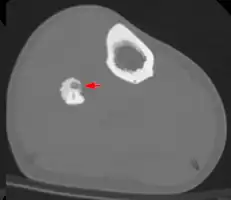

Radiographs in osteoid osteoma typically show a round lucency, containing a dense sclerotic central nidus (the characteristic lesion in this kind of tumor) surrounded by sclerotic bone. The nidus is seldom larger than 1.5 cm.

The lesion can in most cases be detected on CT scan, bone scans and angiograms. Plain radiographs are not always diagnostic. MRI adds little to the CT findings which are useful for localisation. Radionuclide scanning shows intense uptake which is useful for localisation at surgery using a hand held detector, and for confirmation that the entire lesion has been removed.[8][9]

2. CT scan showing an osteoid osteoma of the fibula with a clearly visible nidus -

Nidus demonstrated by high resolution CT